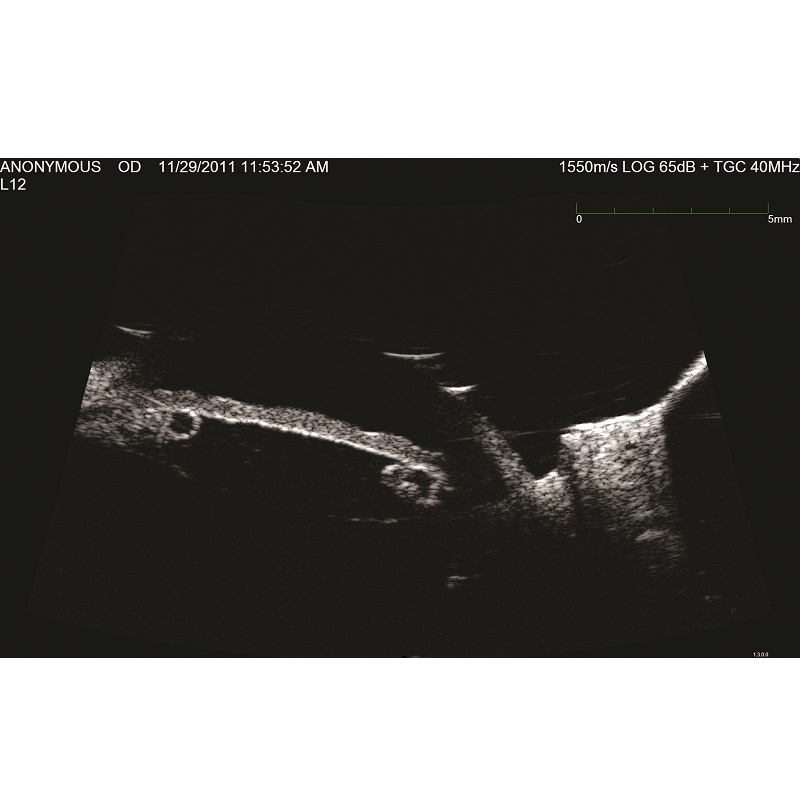

Dzięki dostosowanej konfiguracji trybów A-Scan i B-Scan, Eye Cubed spełnia wszystkie potrzeby w zakresie diagnostyki ultrasonograficznej zarówno w odcinku tylnym, jak i przednim. Tryb UBM 40 MHz umożliwia widzenie struktur oka wyraźniej niż kiedykolwiek wcześniej. Niezależnie od tego, czy mierzymy szczelinę między bruzdą w celu dokładnego określenia rozmiaru ICL, czy kąt przed irydotomią laserem YAG, jest to funkcja, która reprezentuje to, co najlepsze w ultrasonografii o wysokiej rozdzielczości. W trybie skanowania B-Scan 10 MHz Eye Cubed świetnie poradzi sobie z wykryciem nawet najmniej widocznych schorzeń.

Prezentacja A (tak/nie): Tak

Prezentacja B (tak/nie): Tak